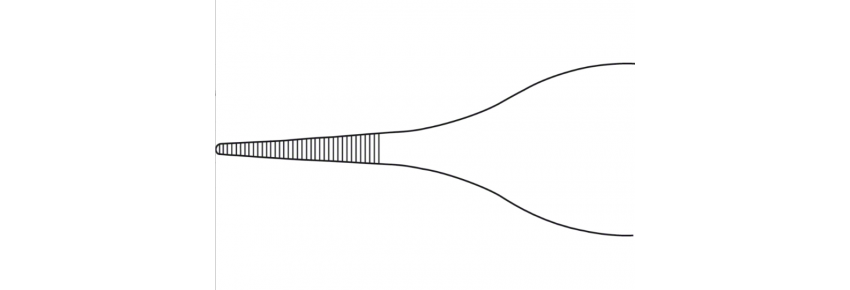

ADSON (MICRO) forceps, delicate, straight, 120 mm (4 3/4") with flat tips and serrated jaws of 0.90 mm. Reusable, latex-free, non-sterile, and equipped with direct UDI marking. Ideal for surgical disciplines that require gentle manipulation of tissues: plastic surgery, pediatric, spinal, vascular, cardiothoracic, dental, neurosurgery, and general.

The ADSON (MICRO) 120 mm forceps are designed for a secure and precise grip on delicate tissues thanks to the flat tip and serrated jaws. The straight geometry and jaw width of 0.90 mm make them ideal for procedures requiring maximum control without damaging the tissue.